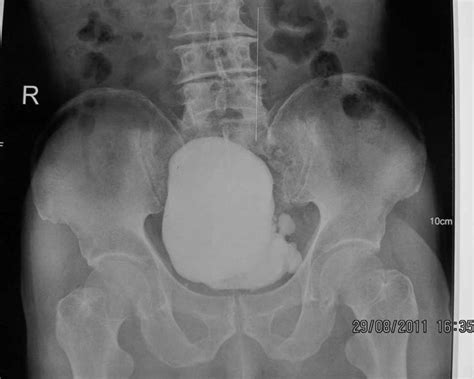

Diagnosing a Urinary Bladder Diverticulum requires imaging to visualize the bladder structure. Urologists typically utilize a combination of the following methods:

Cystogram (Voiding Cystourethrogram) Uses contrast dye and X-rays to see the shape of the bladder while filling and emptying.